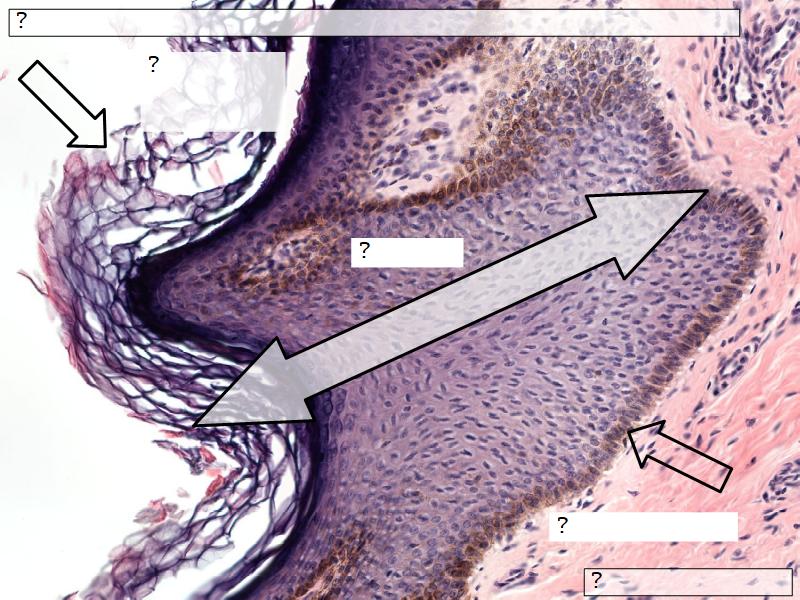

What are the main morphological features of the nipple?

Morphology

- Covered with skin

Skin

- Keratinized stratified squamous epithelium